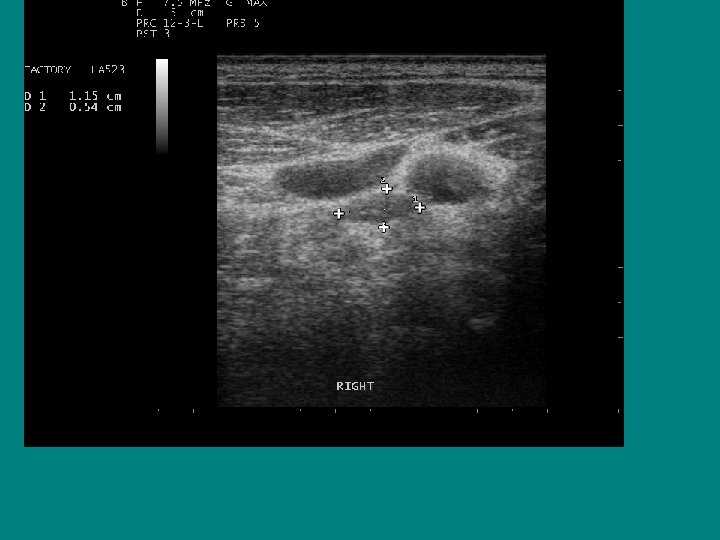

SEARCH FOR RECURRENT/RESIDUAL DISEASE • HYPOECHOIC MASS, LIKELY LYMPH NODE • AP/T 0. 7 CM !!

Now to evaluate this lymph node! • What are my options? a) should we have this resected ? b) check a whole body scan at 6 months c) Biopsy it

Ultrasound characteristics of a benign lymph node Ø Flattened or oval ( AP/T < 0. 5 Ø Echogenic Hilus Ø Hilar Flow on Doppler

Best ultrasound criteria for malignancy • Short to long axis diameter ratio of more than 0. 5 • It has 75 % sensitivity, 81 % specificity • 79 % accuracy

Does size help predict a malignant lymph node? • NO ! • Size doesn’t matter, • Border doesn’t help either

AP/T 0. 79/1. 45= 0. 54 !